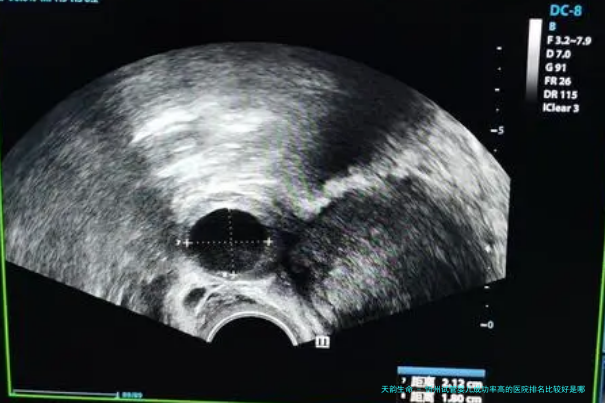

1.诊断和检查费用:医治前的身体检查和诊断是必要的,这部分费用一般来说包括血液检查、超声检查和其他相关测试。